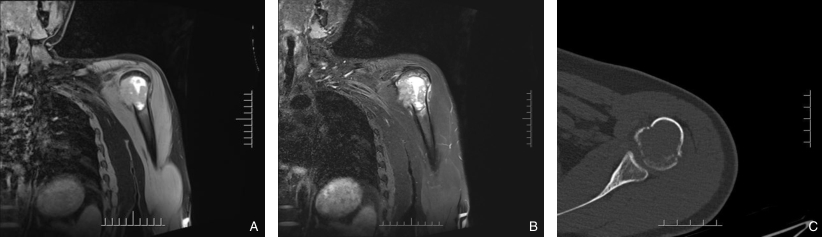

图1 MRI与CT资料 A-B:MRI示,左肱骨上段短-等T1等-长T2信号肿块,突破骨皮质;C:CT示,左侧肱骨上段溶骨性骨质破坏Fig.1 MRI and CT findings A-B: MRI shows a mass with short-to-isointense signal on T1-weighted imaging and iso- to hyperintense signal on T2-weighted imaging in the upper segment of the left humerus, with cortical bone destruction; C: CT shows osteolytic bone destruction in the upper segment of the left humerus